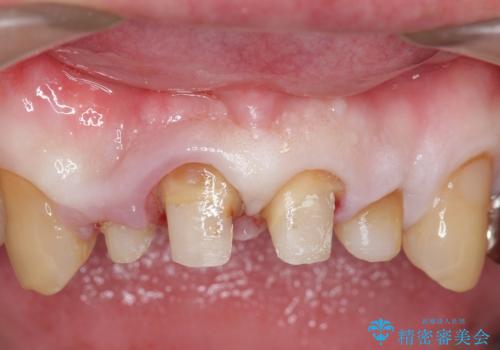

- 前歯の見た目が気になるといらっしゃった方の症例です。

再根管治療後、オールセラミッククラウンによる補綴を行いました。

右上2は歯茎のラインを整えるため歯周外科を行っております。